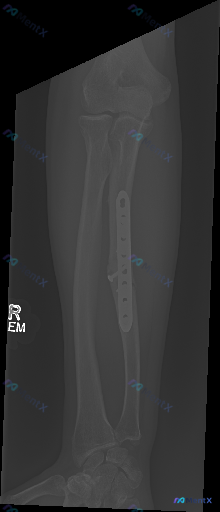

整理到一份前臂X光片(正位)的影像学分析资料,想和大家讨论一下这类术后影像的解读思路。 影像核心表现 - 右侧前臂尺骨干中段可见金属接骨板及螺钉固定 - 接骨板区域尺骨骨皮质连续性已通过内固定重建,未见明显术后继发性移位或断裂 - 桡骨整体骨皮质连续,未见明显骨折线 - 肘、腕关节对位良好,关节间隙...